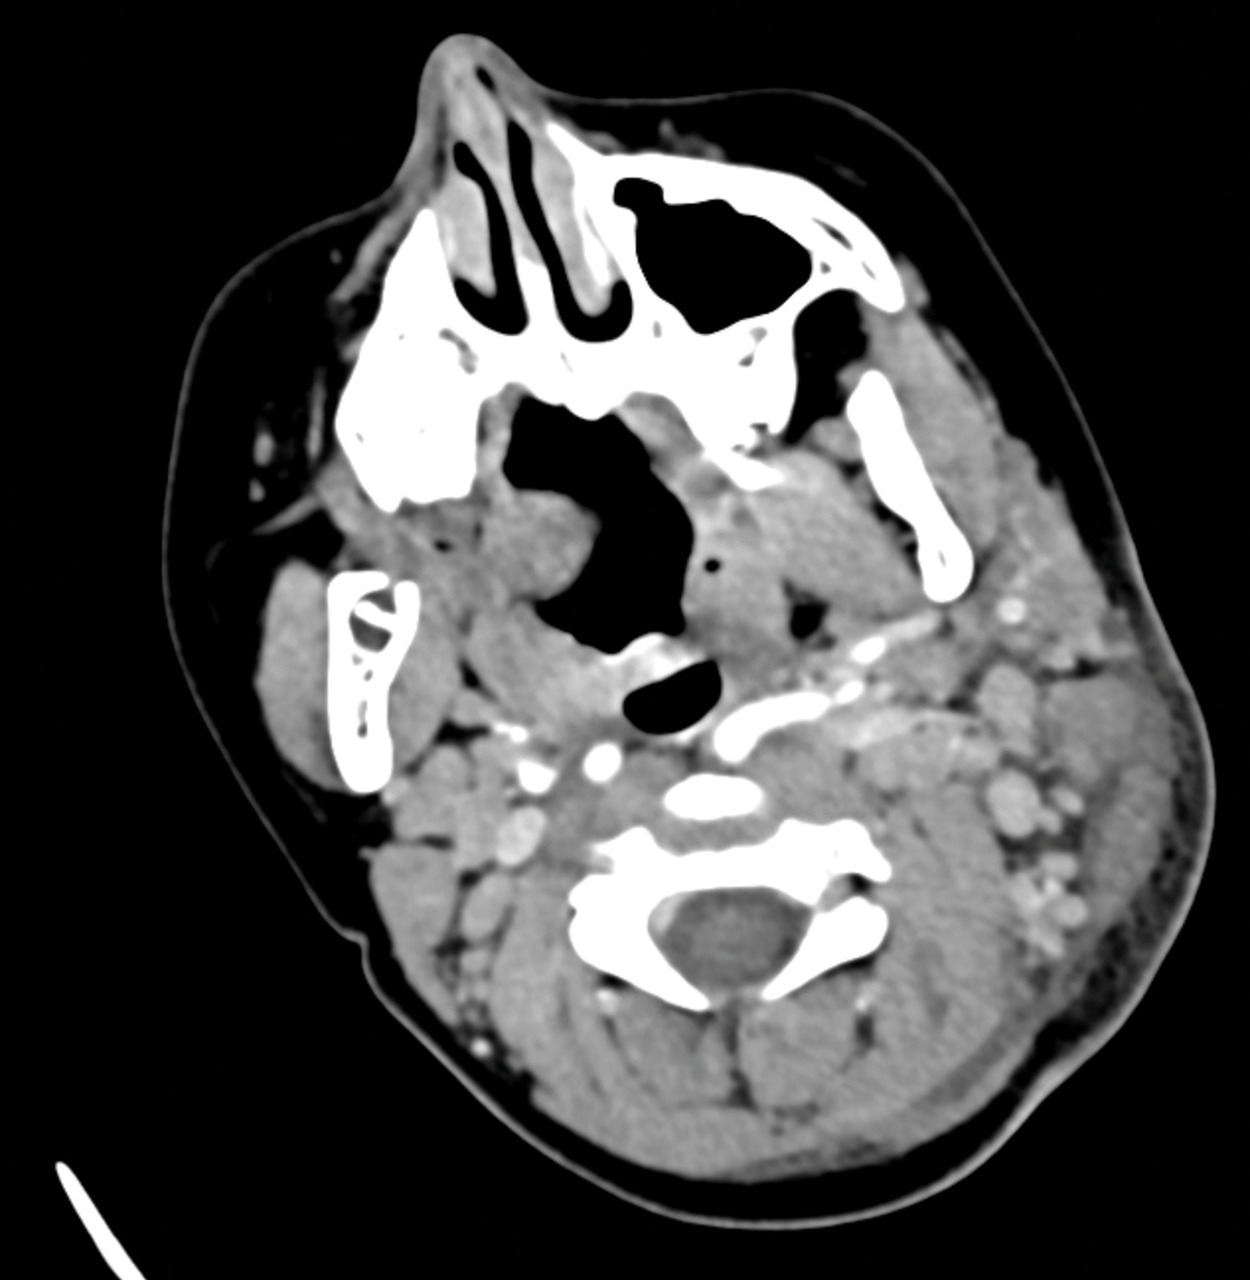

Une jeune fille de 8 ans se présente en consultation de pédiatrie en raison d’un torticolis fébrile. Cinq jours auparavant, elle a été mordue par une tique au niveau du crâne. Lors d’une visite aux urgences quarante-huit heures plus tôt, la tique a été retirée et un traitement par amoxicilline et acide clavulanique a été initié. À l’examen clinique, on retrouve une température de 36,9 °C sous paracétamol, un torticolis du côté gauche avec une adénopathie cervico-occipitale à gauche et une escarre d’inoculation (fig. 1). Les analyses biologiques ne montrent aucune anomalie, dont l’absence de syndrome inflammatoire. Le scanner cervical révèle des adénomégalies inflammatoires sans signe d’abcès (fig. 2). Les cultures bactériologiques et mycologiques prélevées sur l’escarre sont négatives. Face à ces éléments, le syndrome Tibola (tick-borne lymphadenopathy) est suspecté  ; la sérologie Rickettsia demandée s’avère négative. La PCR (polymerase chain reaction) n’a pas été réalisée. Un traitement par macrolides est alors débuté, permettant une nette amélioration clinique en quarante-huit heures.